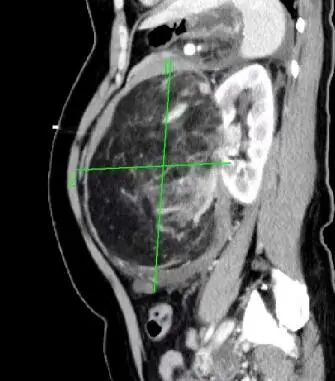

前一段時間,家住惠城區(qū)的林女士(化名)突發(fā)腹痛嘔吐,由120送至惠州市第三人民醫(yī)院急診科。完善全腹部CT后,醫(yī)生發(fā)現(xiàn)患者左腎存在一個巨大腫瘤,直徑約20cm,并伴有破裂出血。

左腎巨大腎錯構瘤約20*20*13cm

經過激烈討論,岳峰主任指出,林女士腫瘤體積巨大,且有破裂出血、周圍滲出較多,盆腔、腹腔積血等情況,腫瘤組織脆弱,周圍結構呈板狀,混雜無界限,手術難度極大,最保險的手術方案就是完整切除整個腎臟。考慮到林女士才四十多歲的年紀以及家屬的期盼,大家決定行左腎部分切除術,完整切除左腎巨大腫瘤,但這一方案,醫(yī)護團隊將要承擔極大的風險!

隨著超聲檢查在體檢中普及,超過一半的偶發(fā)腎錯構瘤在體檢中被發(fā)現(xiàn),隨后經CT或MRI確診。比如林女士,她的腹部增強CT中可見明顯強化的血管結構和無強化的脂肪組織。